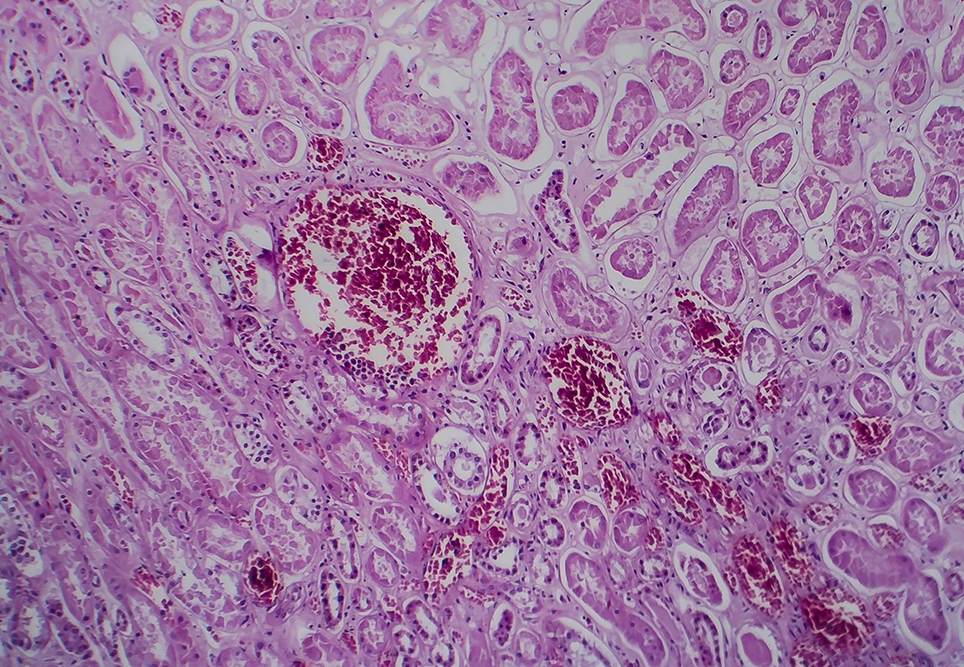

Acute post-strep­to­coc­cal glomeru­lonephri­tis – oth­er­wise known as APS­GN – is an inflam­ma­to­ry dis­ease of the kid­neys fol­low­ing a skin or throat infec­tion with Strep­to­coc­cus pyo­genes, known as group A strep­to­coc­cus (GAS), or occa­sion­al­ly groups C or G streptococcus.

APS­GN stands for acute post-strep­to­coc­cal glomeru­lonephri­tis. It’s an autoim­mune response after expo­sure to a Strep A infec­tion (e.g. ton­sil­li­tis, impeti­go). Autoan­ti­bod­ies that are sup­posed to tar­get the Strep A infec­tion instead tar­get the kidneys.

Pho­to: Dr_​Microbe – stock​.adobe​.com